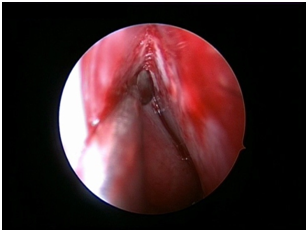

Nasal Endoscopy is done to assess the septal deviation and spurs (Figure 1) ( Figure 2). Septal infiltration is carried out with a solution of 2% Xylocaine with 1: 100,000 adrenaline in the sub-mucosal plane. It is given with a single prick at the inferior most part of the nasal septum at the junction of the septum with the floor of the nasal cavity anterior to the mucocutaneous junction. The infiltration is given at the same point on both the sides (Figure 3). The incision is always given on the deviated side. It is given anterior to the mucocutaneous junction because the skin present at that place is thick and chance of a tear of the flap is less (Figure 4). The mucoperichondrial flap is raised on the deviated side with a Freer’s elevator strictly under vision. The flap is not to be raised beyond the deviated part because the part of the septum posterior to the deviation is not under direct vision (Figure 5) (Figure 6). The caudal end of the septum is then palpated and an incision is given on the cartilage 1cm behind the columella. This 1cm of the cartilage is saved to prevent post operative tip deformities (Figure 7). The cartilage is sliced and the opposite side is entered, the mucoperichondrial flap of the opposite side is then elevated with a Freer’s elevator. A cut is given in the septal cartilage as high as possible. A septal window is created and a Ballenger’s swivel knife is taken and lodged in the place where the cartilage was cut. Creation of a septal window thus increases the area of exposure (Figure 8) (Figure 9). The flap on the non-deviated side is elevated till the bony-cartilaginous junction.

Figure 8 Ballenger’s knife- septal window.

Figure 9 Exposure after septal window.